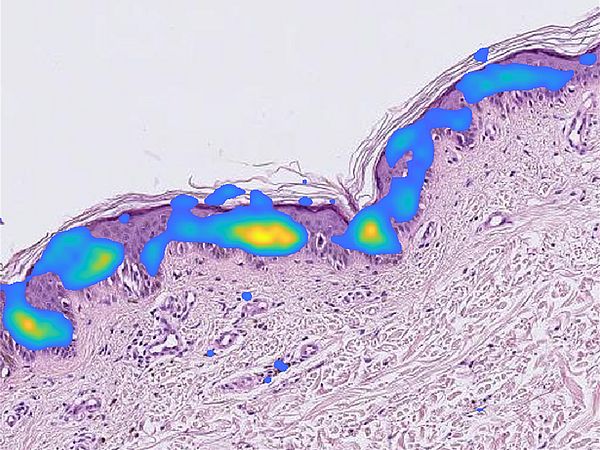

Visualisierung von KI-Ergebnissen zur Krebserkennung

Dieses Projekt zielt daher auf die Bearbeitung eines derartigen prototypischen Problems der digitalen Pathologie sowie auf die Analyse und methodische Umsetzung von mathematisch fundierten Verfahren zur Data Augmentation über neuronale Netze/ Deep Learning. Die AG Technomathematik der Universität Bremen koordiniert dieses Verbundprojekt und ist auf der wissenschaftlichen Seiter mit dem Teilprojekt Invertierbare Netzwerkarchitekturen zur Data Augmentation beteiligt. Hier werden invertierbare Netzwerkarchtitekturen (i-RevNet, learned Mixup) zur Data Augmentation analysiert und zur Erweiterung der Datenbasis bei einer histopathologischen Anwendung eingesetzt.